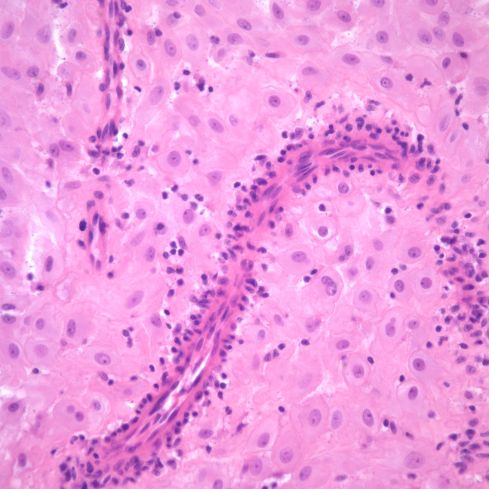

Fig 6b: A higher power of one of the spiral arteries in the previous section demonstrates the lymphocytic appearance of the inflammation. H&E 40x